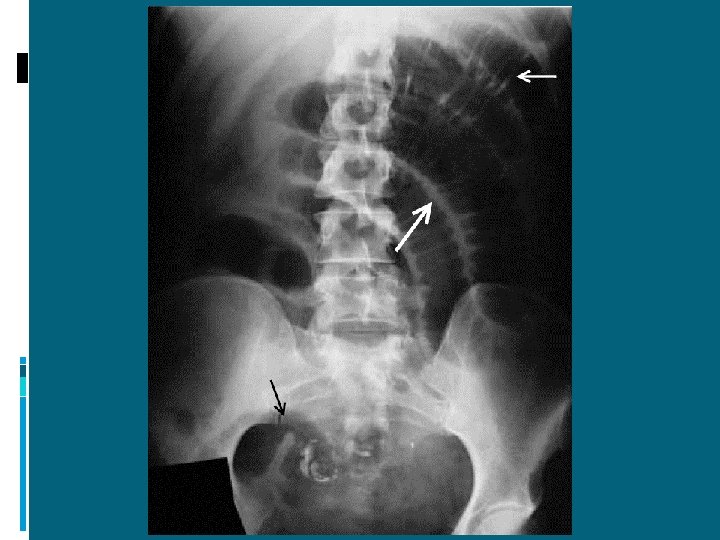

PERITONITI: DIAGNOSI Anamnesi Esame semeiologico Esami ematochimici Rx diretta addome Ecografia (TC)

Perforazione di organo cavo: pneumoperitoneo

Pneumoperitoneo

ILEO MECCANICO: DIAGNOSI RX DIRETTA ADDOME IN ORTOSTATISMO: presenza di livelli idroaerei